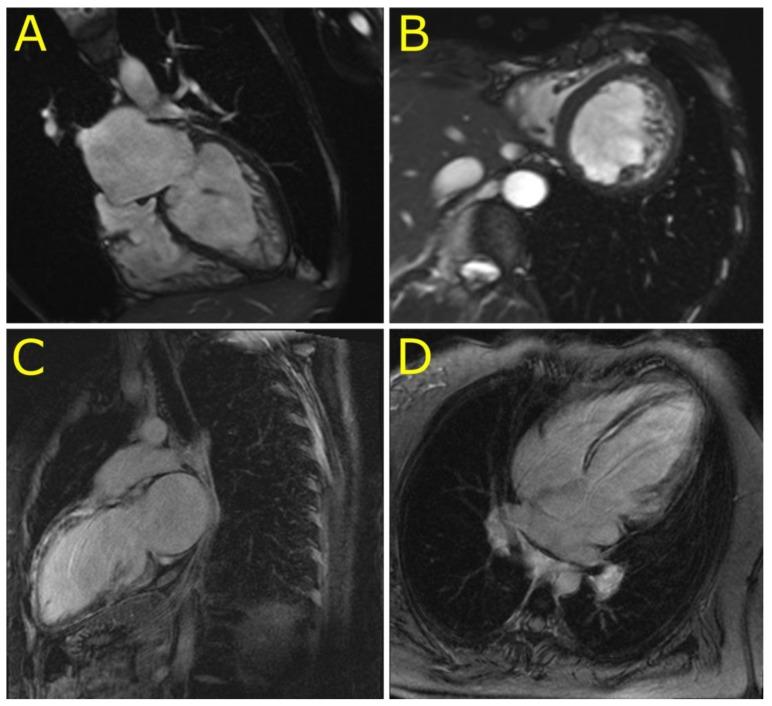

The pleomorphic clinical presentation makes the diagnosis of desminopathy difficult. We aimed to describe the prevalence, phenotypic expression, and mitochondrial function of individuals with putative disease-causing desmin (DES) variants identified in patients with an unexplained etiology of cardiomyopathy. A total of 327 Czech patients underwent whole exome sequencing and detailed phenotyping in probands harboring DES variants. Rare, conserved, and possibly pathogenic DES variants were identified in six (1.8%) probands. Two DES variants previously classified as variants of uncertain significance (p.(K43E), p.(S57L)), one novel DES variant (p.(A210D)), and two known pathogenic DES variants (p.(R406W), p.(R454W)) were associated with characteristic desmin-immunoreactive aggregates in myocardial and/or skeletal biopsy samples. The individual with the novel DES variant p.(Q364H) had a decreased myocardial expression of desmin with absent desmin aggregates in myocardial/skeletal muscle biopsy and presented with familial left ventricular non-compaction cardiomyopathy (LVNC), a relatively novel phenotype associated with desminopathy. An assessment of the mitochondrial function in four probands heterozygous for a disease-causing DES variant confirmed a decreased metabolic capacity of mitochondrial respiratory chain complexes in myocardial/skeletal muscle specimens, which was in case of myocardial succinate respiration more profound than in other cardiomyopathies. The presence of desminopathy should also be considered in individuals with LVNC, and in the differential diagnosis of mitochondrial diseases.